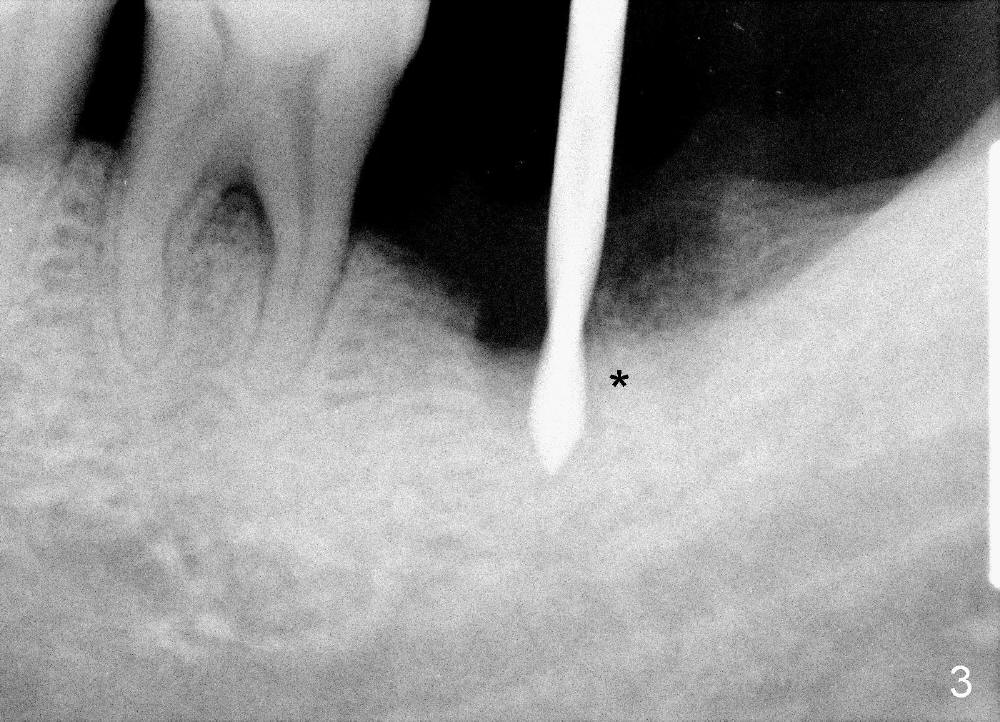

A 51-year-old man has generalized chronic periodontitis. The mesial root of #18 has vertical fracture (Fig.1*) with infection. The patient agrees extraction (Fig.2) and immediate implant. The septum is thin. The pilot drill drops into either the mesial (Fig.3) or distal sockets. Furthermore it is difficult to control pain probably due to severe infection (Fig.2 >: mesiobuccal erythema and edema). Repeated local infiltration does not alleviate pain associated with drilling. Block anesthesia has to be administered (one carpule of 2% Lidocaine with 1:100,000 Epinephrine). Damage to the inferior alveolar nerve (Fig.1 red dashed line) increases. On the other hand, osteotomy through the socket of the tooth with periodontits is easier because of shallow socket. Retraction of the buccal gingiva can reveal the bottom of the socket. We will increase the depth slowly until a tap obtains initial stability. The worst scenario is that active hemorrhage from the socket bottom is encountered initially. The nerve injury can be reduced minimally.

How about flatten the septum (Fig.4 white lines; from inset A (post extraction) to B)? When the septum is level with the mesial and distal sockets, a drill easily penetrates the middle of the socket (Fig.3 inset C). With strict control of depth, the osteotomy increases until a 6x14 mm tap gets initial binding to the socket (Fig.5: depth 11 mm). After increase in the depth by 1-2 mm, PA is taken with a 7x14 mm tap (Fig.6). There is a gap that the tap or the corresponding implant can engage further (between arrowheads). After increase in the diameter in the bottom of the osteotomy, a 7x11 mm implant is placed with insertion torque between 45 and 50 Ncm; the threads of the implant have tight contact with the bone (Fig.7). With the large diameter implant, the socket opening is closed without too much tension (Fig.8). The wound is protected with perio dressing. Postop there is no paresthesia. Pain is controlled by Hydrocodon/Acetaminophen. A long acting local anesthetic (Marcaine) should have been used immediately postop. Next morning, the patient is pain free. A short implant should be used in a critical area such as the lower 2nd molar where the inferior alveolar nerve is nearby. However, the implant is found unstable 1 month postop.